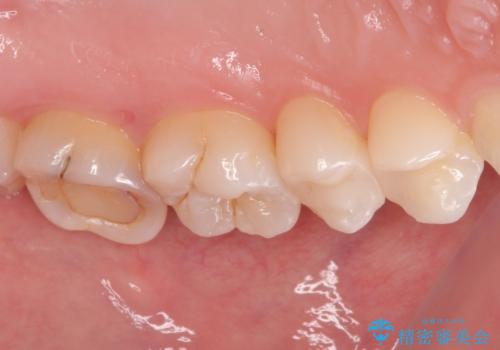

ラバーダム防湿下でコンポジットレジンを除去しファイバーコア築造を行い、オールセラミッククラウンに適した形に整えました。